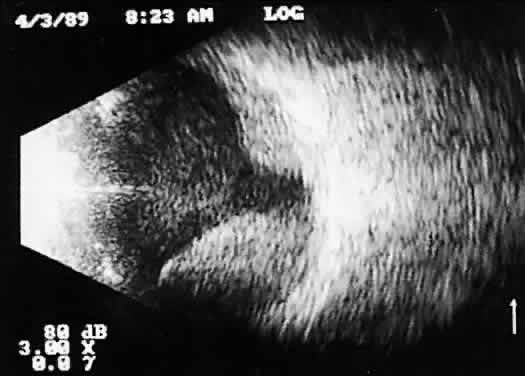

Fig. 9. Contact B-scan: total retinal detachment, anteroposterior view. Characteristic V-shaped appearance with attachment to the optic nerve head.